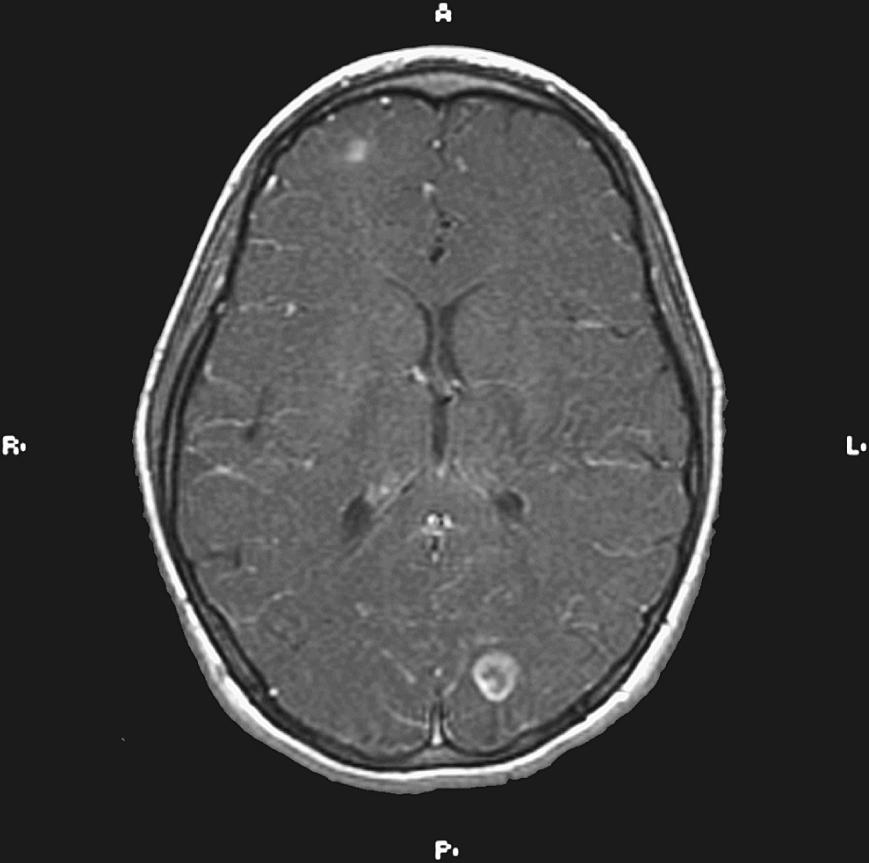

The implementation of subacute endocarditis prophylaxis before dental and surgical procedures in patients with CHD has greatly reduced the incidence of bacterial endocarditis, but it has not improved mortality, which remains at 11.1% ( ). Approximately one-third of cases of infective endocarditis are associated with neurological complications. These include cerebral embolization, usually in the middle cerebral artery (MCA) territory, meningitis, brain abscess, and seizures ( Fig. 59.1 ). Cerebral mycotic aneurysms complicate 1.2%–5% of cases of infective endocarditis and carry a high mortality rate of 60%. The risk of hemorrhagic transformation of septic infarctions is high and associated with a mortality rate of 80%–90%.

Fig. 59.1, Magnetic resonance image of brain of a 12-year-old girl with congenital heart disease, subacute endocarditis, and brain abscess. The patient presented with fever, headaches, and diplopia.